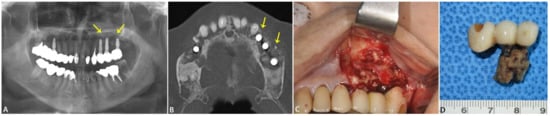

2.1.3. Case 3: Apicoectomy of Fixture Case

| No. 3 | Maxillary sinusitis, retention pseudocyst | #16i | Implant surface of the implant apex | Ti: 71.06% O: 14.44% C: 11.25% | Si: 0.4% Ca: 0.3% | The membrane/biofilm could be observed The morphology of the fixture surface revealed an irregular and defected sandblasted and acid-etched surface Blood cells, fibrin, bacteria, and Ti particles were observed | |

| Normal level of Ti, surface covered by a layer of Ti oxide Trace amounts of Si and Ca | |||||||